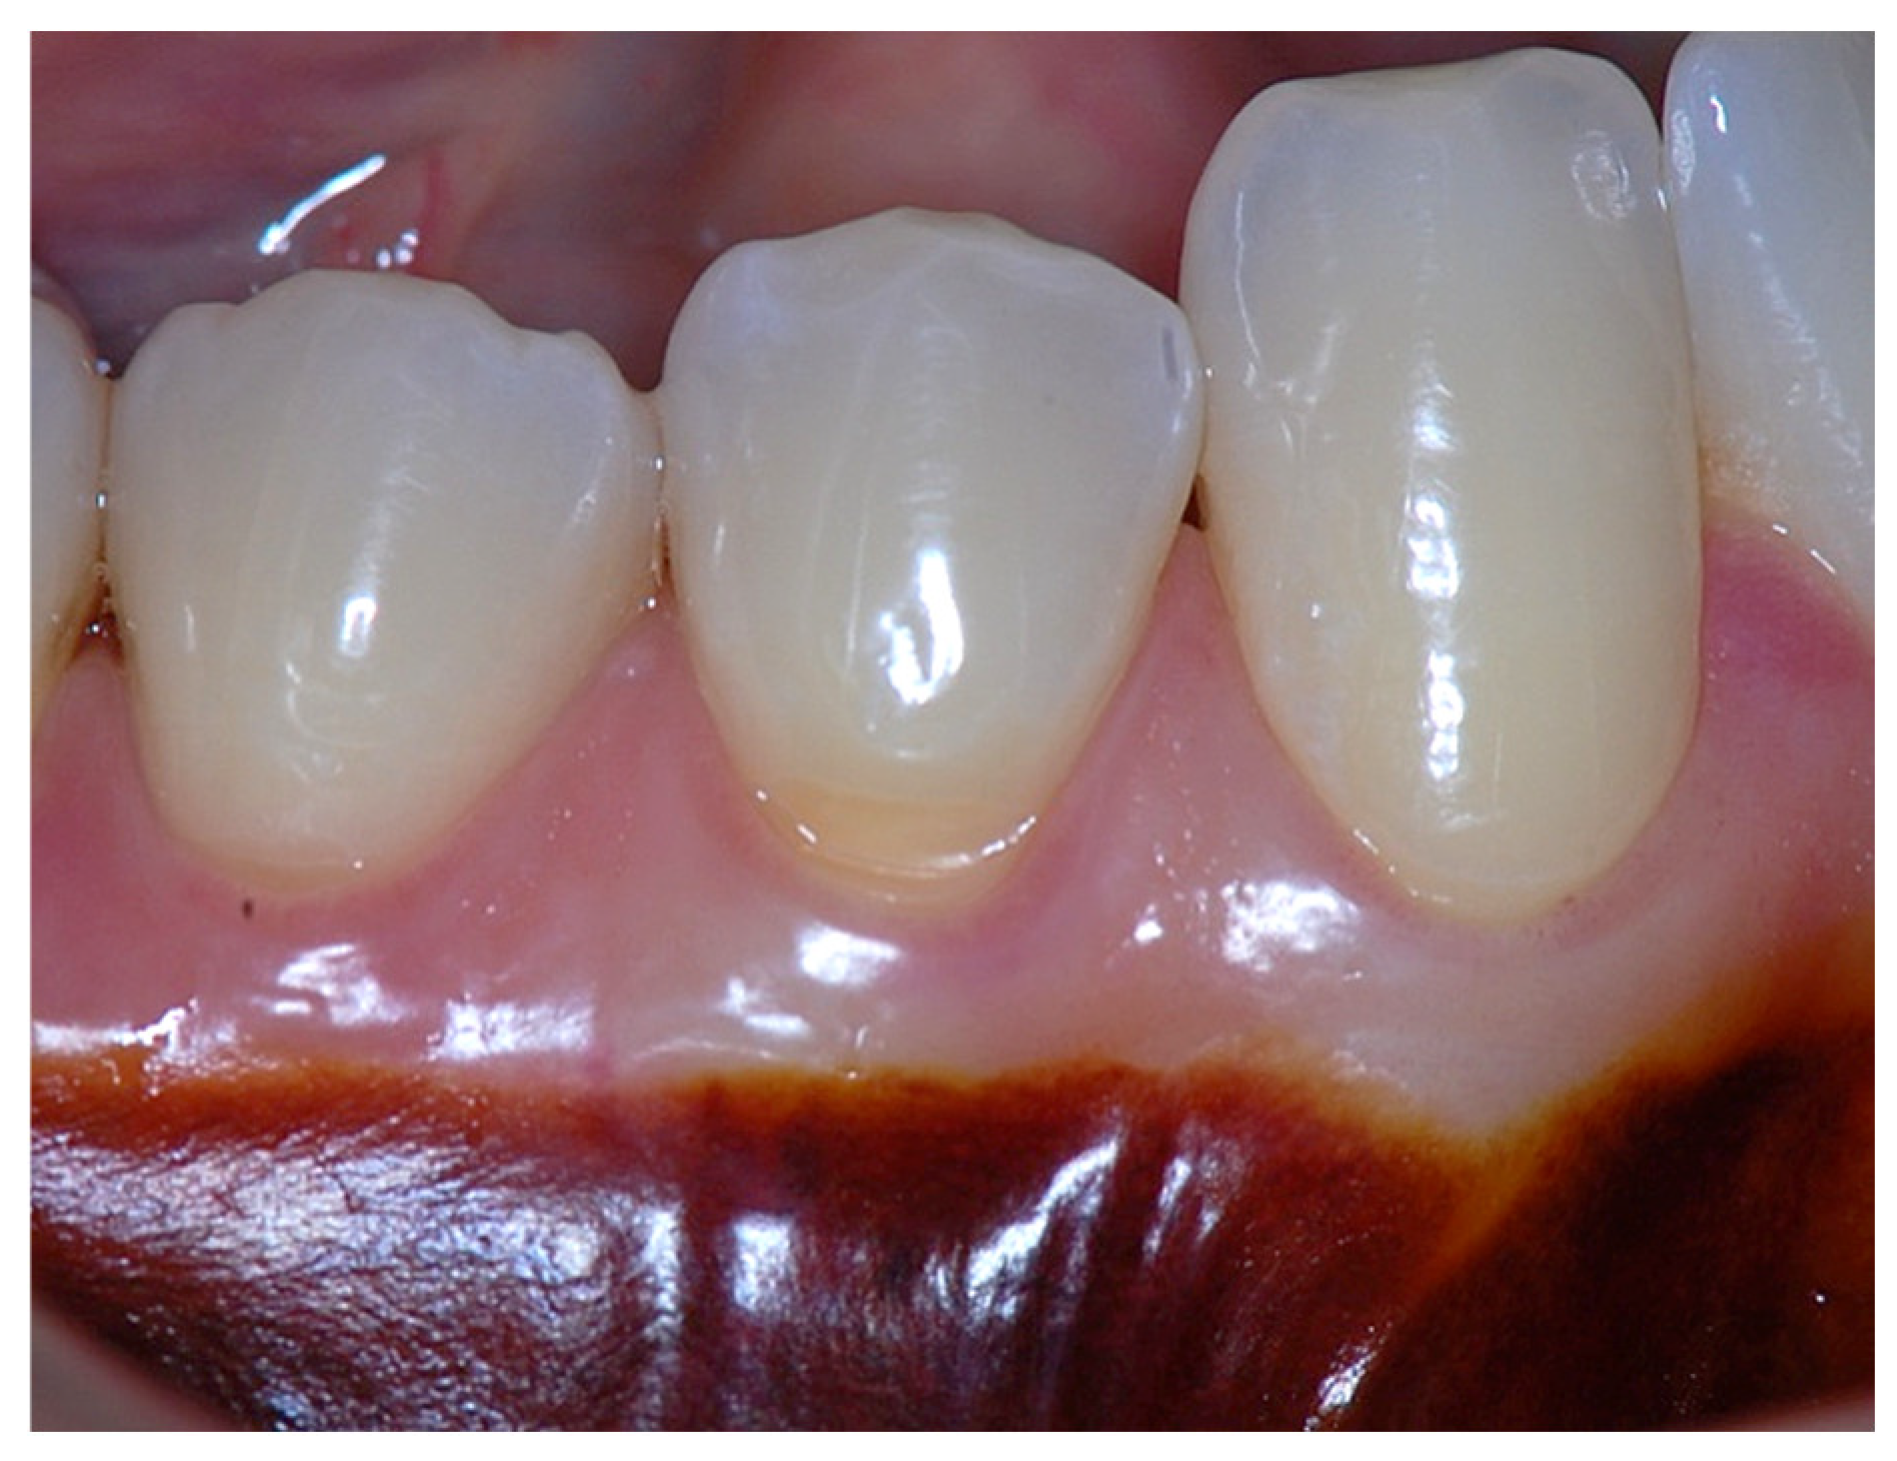

Figure 4. Clinical image of tooth #29 showing an insufficient width of attached gingiva.

In a clinical scenario with 2 mm of keratinized tissue (KT) and a sulcus depth of 1 mm, a stable, firm, and resistant connective attachment is not present [1]. This occurs because most of the connective tissue fibers inserting onto the root surface are associated with non-keratinized, mobile mucosal tissues (Figure 1), which are elastic in nature and therefore unable to stabilize the gingival margin (Figure 4 and Figure 5). Conversely, when these fibers are embedded within keratinized tissue, they are firmly attached to the tooth and bone and are comparatively immobile, thereby contributing to gingival margin stability (Figure 2, Figure 3, and Figure 6).